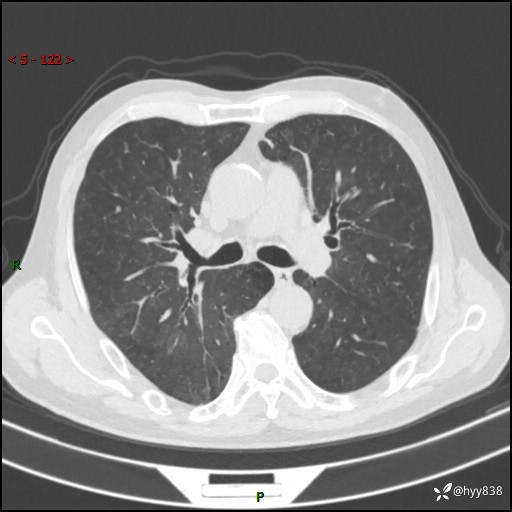

辅助检查:CT

胸部CT平扫